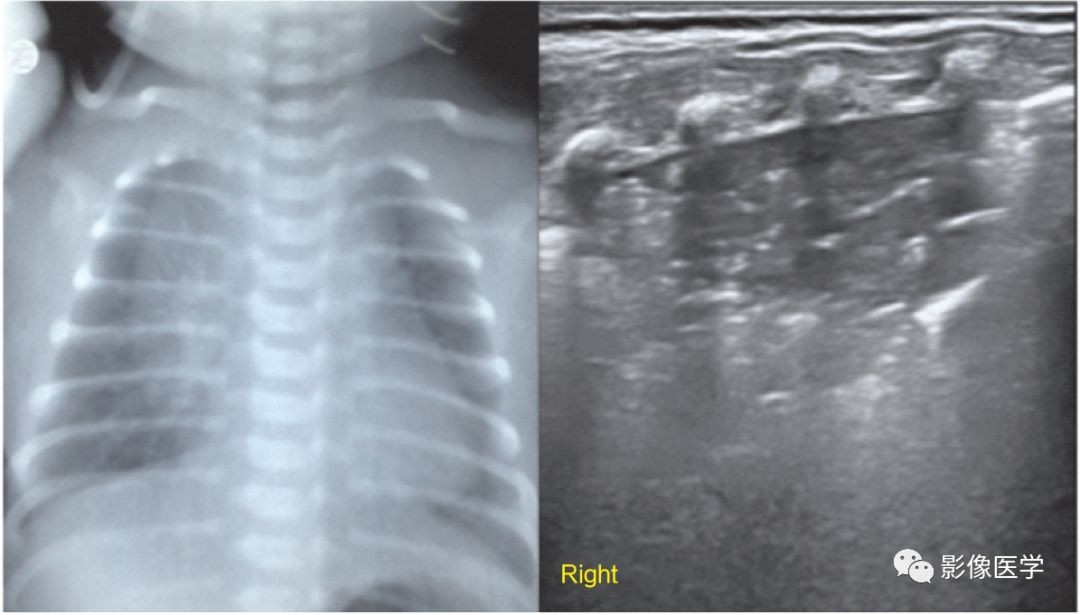

图6-5 宫内感染性肺炎(1)

胎龄37周,剖宫产分娩,出生体重3 700g。无窒息,有胎膜早破史,出生后呼吸困难,发热。血常规:WBC 30×109/L,N81%,PLT 67×109/L,CRP 39mg/L。肺脏超声显示右肺大面积边缘不规则实变区伴支气管充气征,胸膜线存在,A线消失,胸膜腔内可见极少量积液。胸部X线显示新生儿肺炎改变,右肺显著。